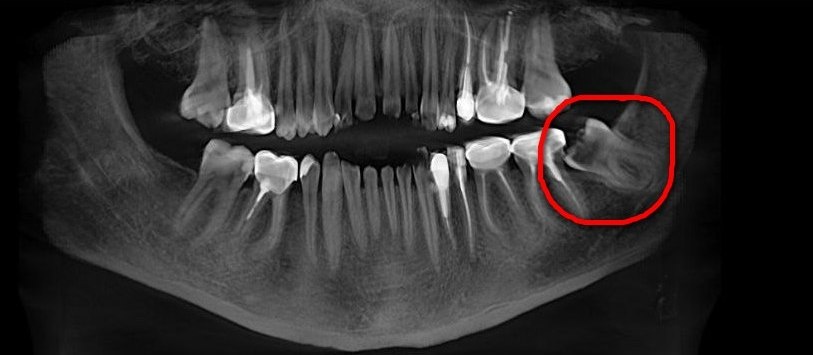

📍 Клинический случай из практики Дениса Сергеевича: пациента долгое время беспокоили ноющие самопроизвольные боли в области зуба мудрости, которые возникали периодически. На осмотре был диагностирован перикоронит. По данным КЛКТ было также выявлено разрушение коронковой части «восьмёрки» и признаки периодонтита (воспаление тканей вокруг верхушки корня зуба), что привело к образованию полостей, в которые стала попадать пища. Это создавало идеальные условия для размножения бактерий и затрудняло гигиену. Постепенно развился кариес, перешедший в осложнённую форму - в данном случае в периодонтит. Учитывая степень поражения и невозможность полноценного лечения, такой зуб было рекомендовано удалить.